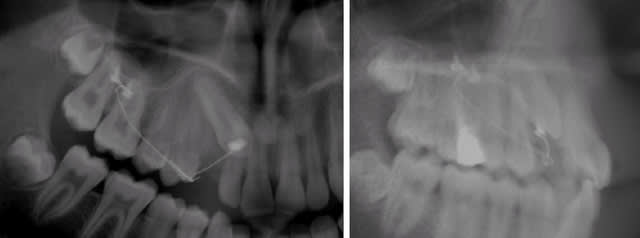

Tout d'abord, où est-elle exactement ? En vestibulaire ou en palatin ?

La canine , sur la pano , est plus nette que les autres dents. Donc plus proche du film radio , elle est donc vestibulaire.

Je rappelle que la pano est une tomo, donc la notion de netteté liée à la proximité du film n'a pas lieu d'être.

Notez bien que ces 2 radios sont suffisantes pour déterminer la position de la canine. A vous de trouver "le truc" (que personne ici n'a encore évoqué).

1. sur l'OPT, quand on regarde la dent, elle a l'air un agrandie, plus large que la 23 et bien souvent c'est lié à une position palatine avec une histoire distance-film-foyer.

2. la cuspide de 13 est superposée à la centrale sur l'OTP elle devrait ainsi apparaître en avant de la 11 sur la radio de profil si elle était vestibulaire. Et comme ce n'est pas le cas, la dent doit être palatine.

3. on voit bien distinctement la racine de 12 qui se voit par transparence supperposée à la couronne de 13. l'apex est bien visible, la dent semble bien verticale et donc l'apex vestibulaire. En gros y'a pas de place en vestibulaire pour caser une canine incluse. Car parfois on a des latérales très vestibulo-versée et on distingue mal les apex sur les OTP.

sur la pano, la canine se superpose à la centrale, alors que sur l'autre cliché: elle est en en arriere.

Oui, c'est juste, vous avez raison.

C'est très simple quand on a une radio de profil en plus de l'OTP (les 2 clichés basiques d'un bilan orthodontique) : une canine palatine y apparait verticale et une canine vestibulaire horizontale, couronne vers l'avant, comme sur l'exemple que je vous joins avec les confirmation chir.

Il n'y a que pour les cas relativement peu fréquents où elle est entre les 2 qu'il est souhaitable d'avoir un examen complémentaire.